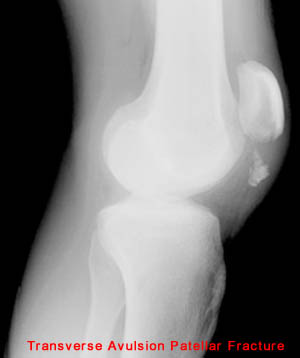

25) Name the abnormality shown in the image below.

26) How can a patellar fracture be distinguished from bipartite or multipartite patella?

Bipartite and multipartite patella have rounder edges that don't fit together as well.

28) Name the abnormality shown in the image below.

29) Give the specific name for the fracture type shown in the image above. Avulsion